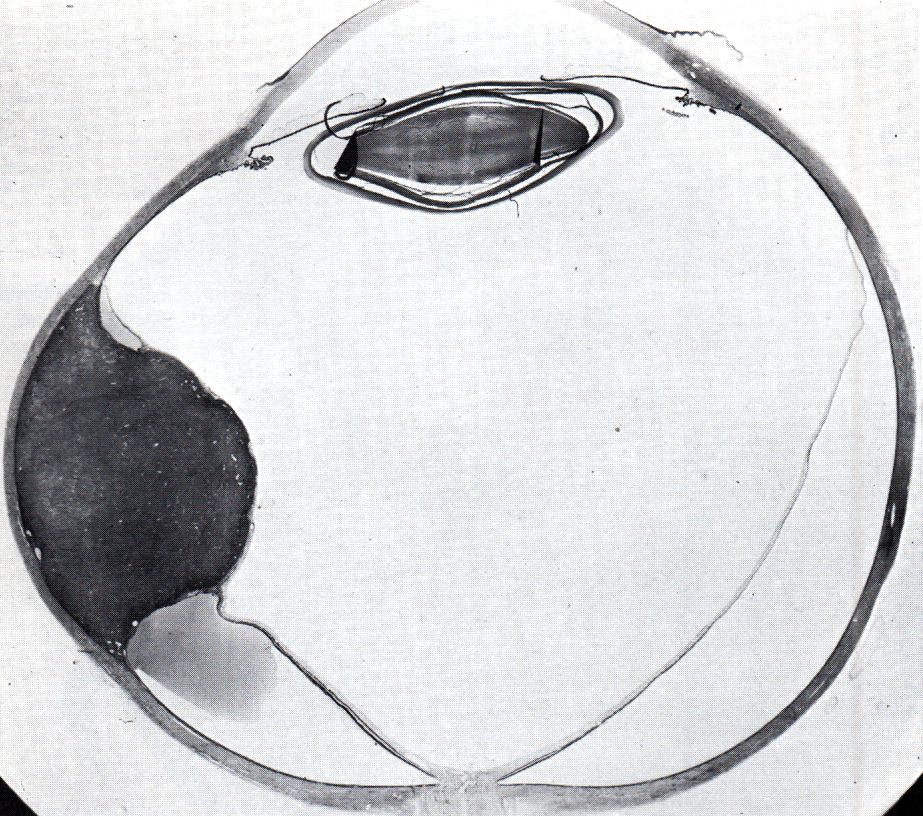

Chorion-Melanom

Therapie Resektion, Enukleation, Brachytherapie, stereotaktische Bestrahlung.

Studien COMS III: Collaborative Ocular Melanoma Study, Plaque - Brachytherapie.